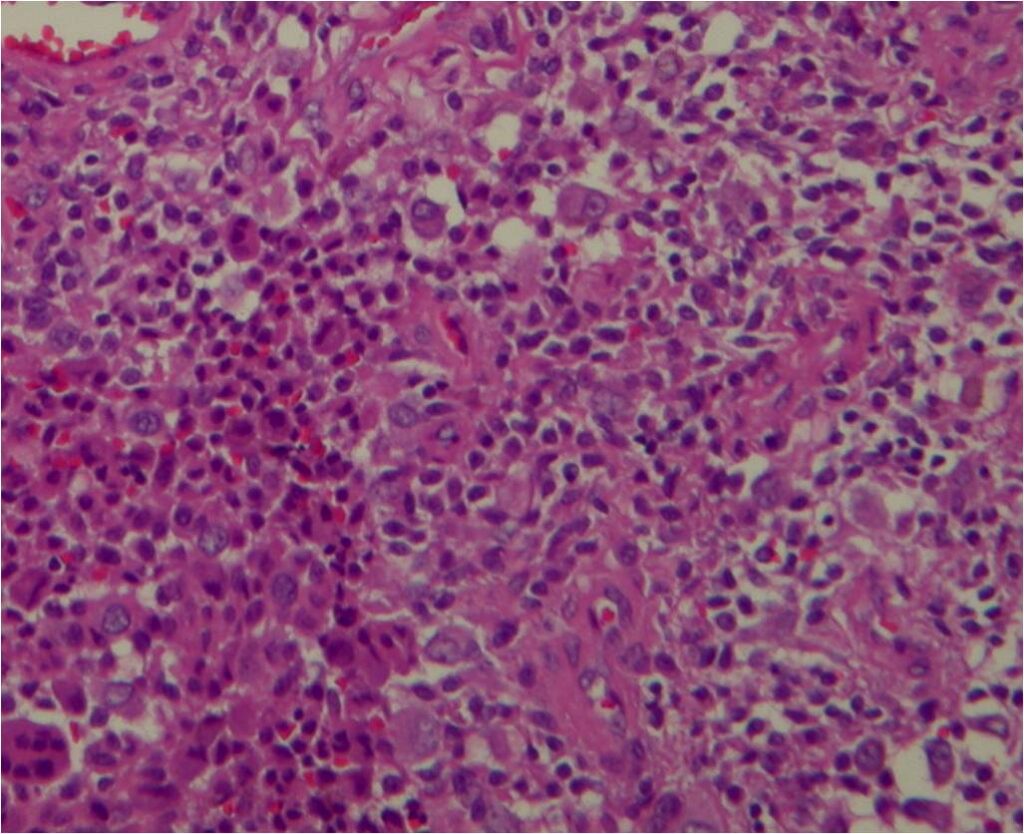

Microscopic

• Dense fibrous tissue divides tumor

• Gives nodular appearance

• Cells

• Small, round to oblong, often reniform or clefted nuclei

• Sometimes prominent nucleoli

• Oblong

• Frequently blend with spindled forms

• Variable numbers of giant cells

• Similar type of nuclei

• Usually contain 8-10 nuclei

• Xanthoma cells

• Sparse mitotic figures

• Low mitotic activity (3 to 5 mitosis x 10 HPF)

• Rarely necrosis is seen

Fig. 7-10: Microscopic pathology. Abundant small hystiocyte-like cells, numerous giant cells and xanthoma cells. In higher magnification images some foamy histiocytes are visible. No mitotic activity is present. Hemosidering deposition is common.